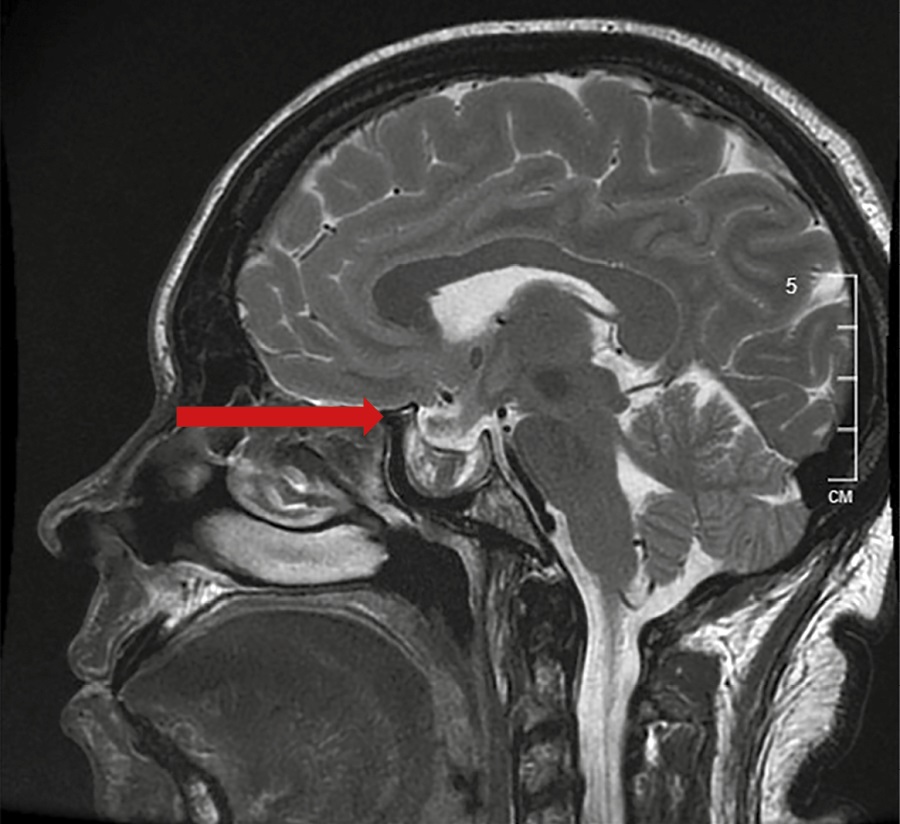

На МРТ головного мозга с контрастным усилением — МР-признаки перенесенной апоплексии в аденому гипофиза: в полости турецкого седла с распространением в левый кавернозный синус визуализируется образование неправильной формы, неоднородного МР-сигнала за счет кистозного компонента в центральных отделах с гиперинтенсивным на Т1-ВИ ободком по контуру. При сравнении со снимками МРТ от 31.08.2023 отмечается уменьшение размеров макроаденомы гипофиза с 25х22х26 мм до 26х13х22 мм (рис. 1).

Рисунок 1. МРТ головного мозга с контрастным усилением от 23.11.2023. МР-признаки перенесенной апоплексии в аденому гипофиза.

Таким образом, подтверждена ремиссия акромегалии вследствие апоплексии в аденому гипофиза, нейрохирургическое лечение не показано, установлен гипопитуитаризм. Инициирована терапия гидрокортизоном в дозировке 10 мг в 08:00 и 5 мг в 16:00. Через неделю к терапии добавлен левотироксин натрия 50 мкг утром. На фоне проводимой терапии пациентка отметила значительное улучшение самочувствия.